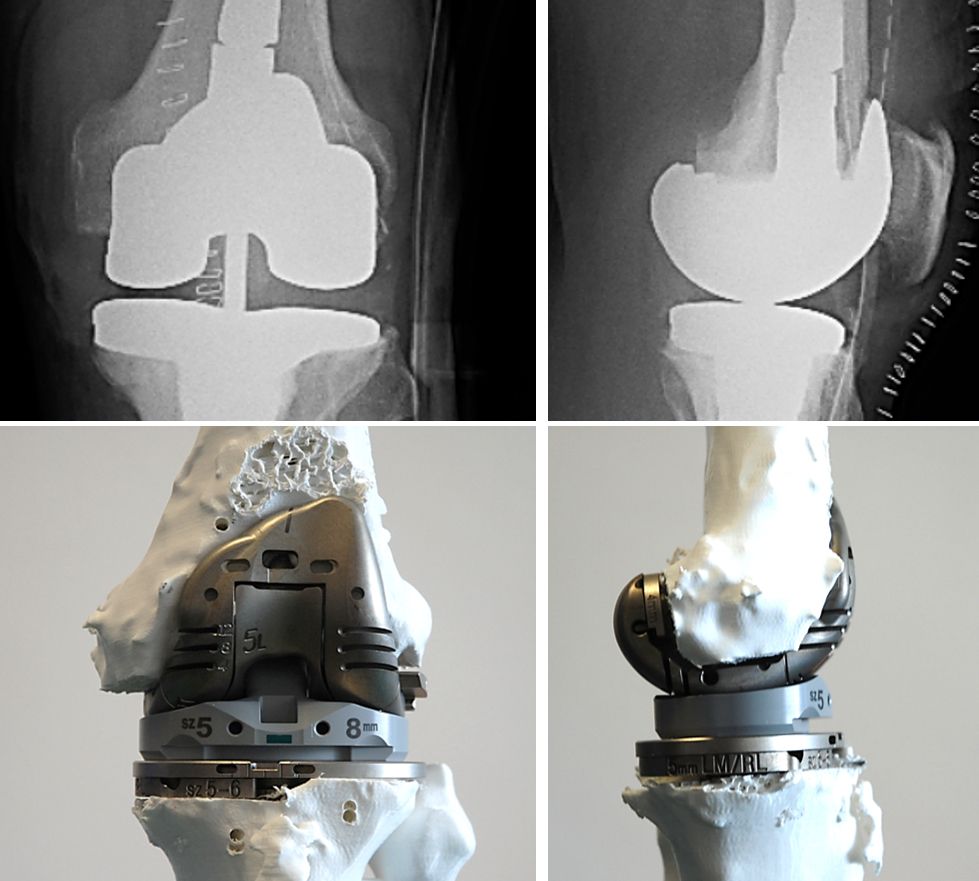

A few days before surgery, the surgeon and nurse can "implant" the real prosthesis and perform the upcoming procedure (fig. 6-8) using real instrumentation on the newly produced 3D model to determine the size of the components (fig. 9) and the need for wedges or cones, if necessary, to restore the correct position and rotation of the joint axis.

During implantation all the different options for stem length and offset, spacers, blocks and sizes can be preselected and every feature of the implant is already known and can be assembled. In many cases the preop plan fits very well with the final intraoperative solution (fig. 10-12).

The preoperative use of the 3D model (Fig. 17) allows the surgeon to plan the operation, to study anatomy and bone loss and to identify the best option for reconstruction, with the possibility to switch from one solution to another (e.g. rods or cones, offset..., Figs. 18-20) and to choose the most appropriate one in order to save time and reduce unnecessary manoeuvres during the operation.

The economic aspect must also be taken into account. The 3D model costs about 500 euros, which can be reduced by intensive use, but saves time and other costs. Once the reproducibility of the system is proven (Fig. 22), it will be possible to eliminate all unnecessary materials and instruments from the operating theatre, thus saving costs for storage, sterilisation, transport and operating time.